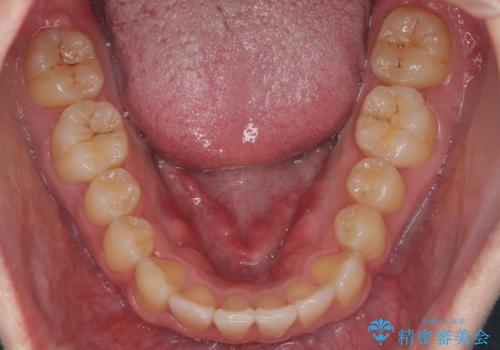

- 前歯のすきまと八重歯を主訴に来院。

左上の乳犬歯が残っており、その下から生えてくるはずの犬歯(永久歯)が左上小臼歯部に萌出していました。

左上の乳犬歯は根もしっかりしていたため、

➀そのまま矯正する。乳歯がいずれダメになったときにそこはブリッジかインプラントを検討する

②乳歯は抜歯し、ブリッジかインプラントを矯正後に入れる

を提案し、➀を選択されました。

将来的にインプラントは希望されないとのことだったため、乳歯の部分は隙間を開けてインプラントを入れる用のすき間を確保するということは特に行いませんでした。

乳歯をそのまま並べたため、上顎の左右の犬歯の幅は非対称になっています。